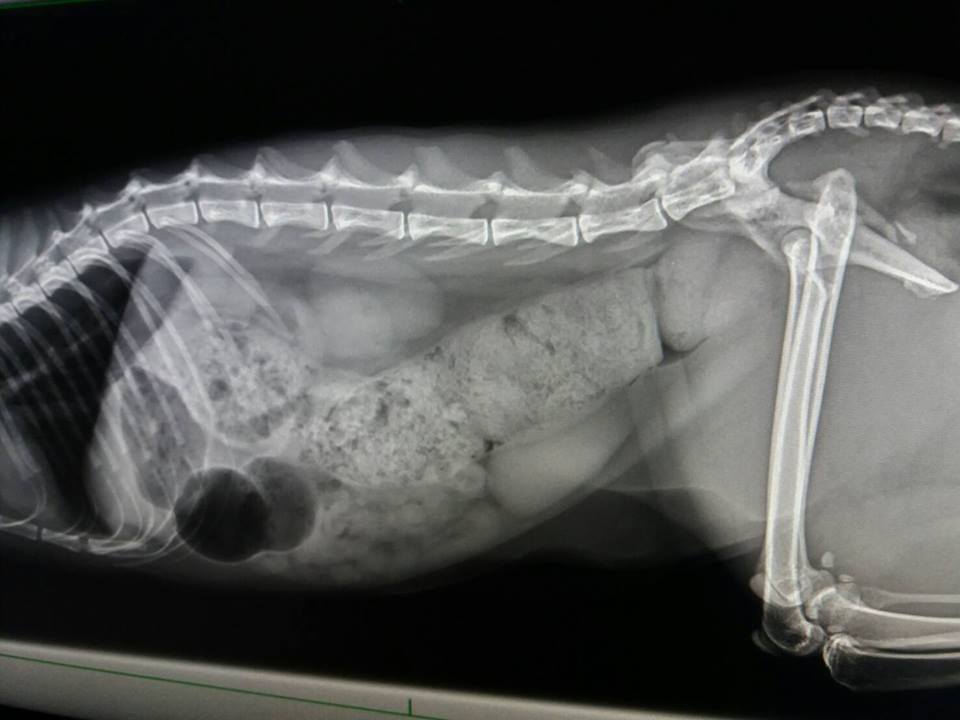

主題: 骨盆腔狹小進行灌腸與追蹤治療的艾咪 申請者姓名: 臺北市支持流浪貓絕育計劃協會 花色: 申請日期: 2017-06-15 11:28:56 申請者部落格: 申請者臉書網址: 所在縣市/合作醫院: 台北市/澄諾動物醫院 治療費用: 6300元 需求人數: 15人 已結案 (2024-06-01 13:27:02) 報名人員: 海郁(已付款)、ocean(已付款)、琪芳(已付款)、林妮妮(已付款)、COCO(已付款)、Jin(已付款)、Karen Chiou x2(已付款)、Tsai Dobbie x2(已付款)、meemee(已付款)、貓步小姐(已付款)、yushi0304 x3(已付款)、 候補人員: 動物病情說明: 因骨盆與腿部骨折而導致骨盆狹小的艾咪,

4/27 澄諾回診 艾咪 3.21KG

【回診狀況】

艾咪又連續沒大便因而再度回診,

X光下發現大腸寬度變大,

認為有一可能導致艾咪雖有大便但無便意,等到積很久後,

後面大便已乾,

認為杜化液可能對艾咪已無太大效果

本日增加軟便劑劑量

且從今日起杜化液提高為5CC,早晚各一次,

飲食部分即日起加入洋車前子